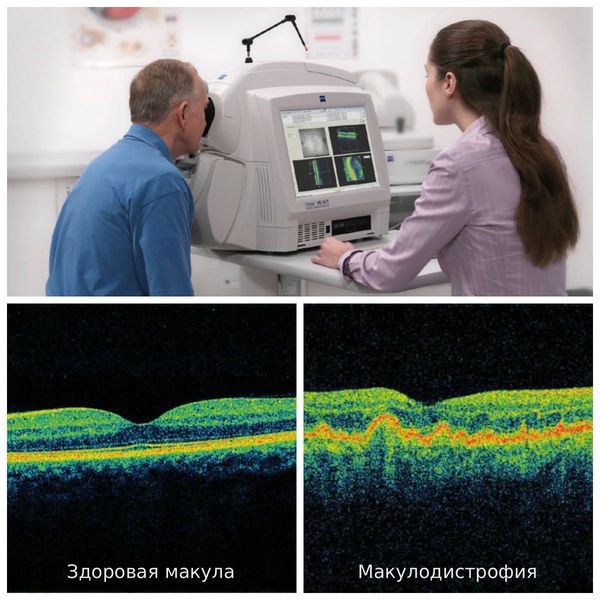

Диагностика зрения: Когерентная томография сетчатки